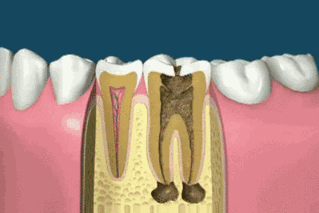

Si la pulpe n'est pas blessée et ne provoque pas de pulpite, il est généralement possible d'obturer directement la dent ! Le prix est également relativement bon marché, il y a généralement plusieurs types de matériaux à choisir, plusieurs centaines de dollars ! Si la pulpe de la dent est suffisamment profonde pour provoquer une pulpite, vous devrez subir un traitement de canal ! Qu'est-ce qu'un traitement de canal ? Cela signifie simplement que le nerf de la dent est tué et qu'une fois le traitement de canal effectué, la dent ne fera plus jamais mal !

Les tarifs des traitements de canal varient d'un endroit à l'autre, certains facturant en fonction du nombre de canaux dans votre dent, et d'autres en fonction du type de dent que vous avez ! En général, les grandes dents et les incisives sont plus chères ! Un traitement de canal coûte entre 1 500 et 3 000 euros pour une seule dent, et comme il faut éliminer la carie à l'intérieur de la dent, il faut aussi faire des plombages.